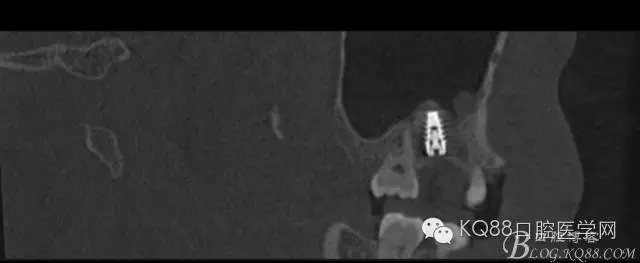

植入后,CBCT

另外一個切面。竇底粘膜完整連續(xù)。可以看到上下咬合的位置關(guān)系。